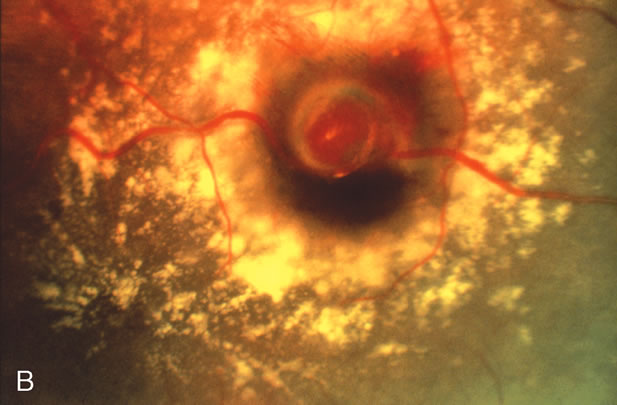

Retinal arterial macroaneurysms often produce retinal edema, circinate hard exudates, and hemorrhage (Fig. 3) into multiple layers of the retina: beneath the retinal pigment epithelium, beneath the retina, within the retina, beneath the internal limiting membrane, between the retina and the posterior hyaloid, and within the vitreous cavity. When the macroaneurysm is obscured by overlying blood, its diagnosis can be challenging.

Fig. 3. A. Color fundus photograph of a macroaneurysm along the inferotemporal arcade with surrounding intraretinal and subretinal hemorrhage. There is retinal edema, hard exudates, and thin subretinal hemorrhage extending into the macula. B. Midphase fluorescein angiography reveals hemorrhage that extends just into the foveal avascular zone, threatening foveal vision. C. Late-phase angiogram reveals staining of the macroaneurysm. D. Color fundus photograph of the same macroaneurysm 6 weeks after laser photocoagulation, demonstrating resolution of the edema and hemorrhage.